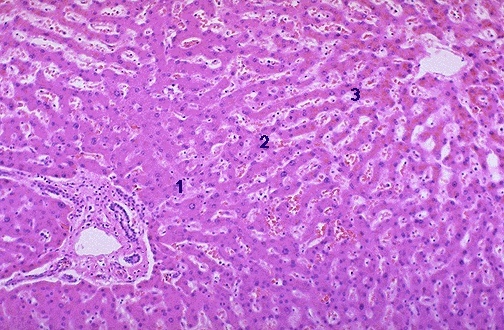

1.Liver

3 zones, with the 3rd zone making up more mature hepatocytes

Blood flows from the portal vein to the central vein.